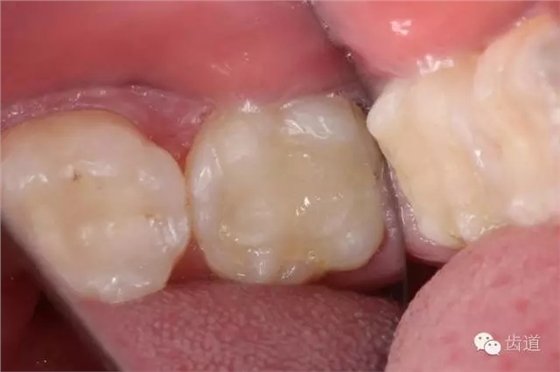

檢查:術(shù)后半年回訪,37牙體及合面嵌體未見(jiàn)缺損及裂紋,邊緣密合,未探及繼發(fā)齲,探痛-,叩痛-,松動(dòng)-,冷水刺激痛-,未探及牙周袋及附著喪失,牙齦無(wú)紅腫,X線片檢查示根尖周膜連續(xù)性恢復(fù),根尖周透射影消失。

1. 術(shù)后半年口內(nèi)照片

2. 術(shù)后半年X線檢查,可見(jiàn)根尖周膜連續(xù)性恢復(fù),根尖周透射影消失